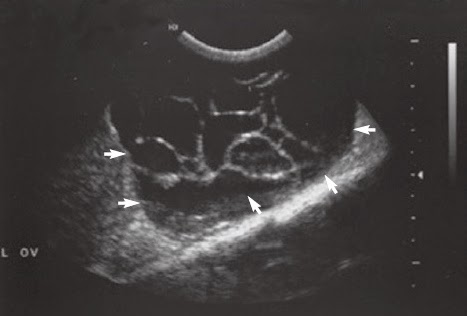

Cistos e tumores ovarianos